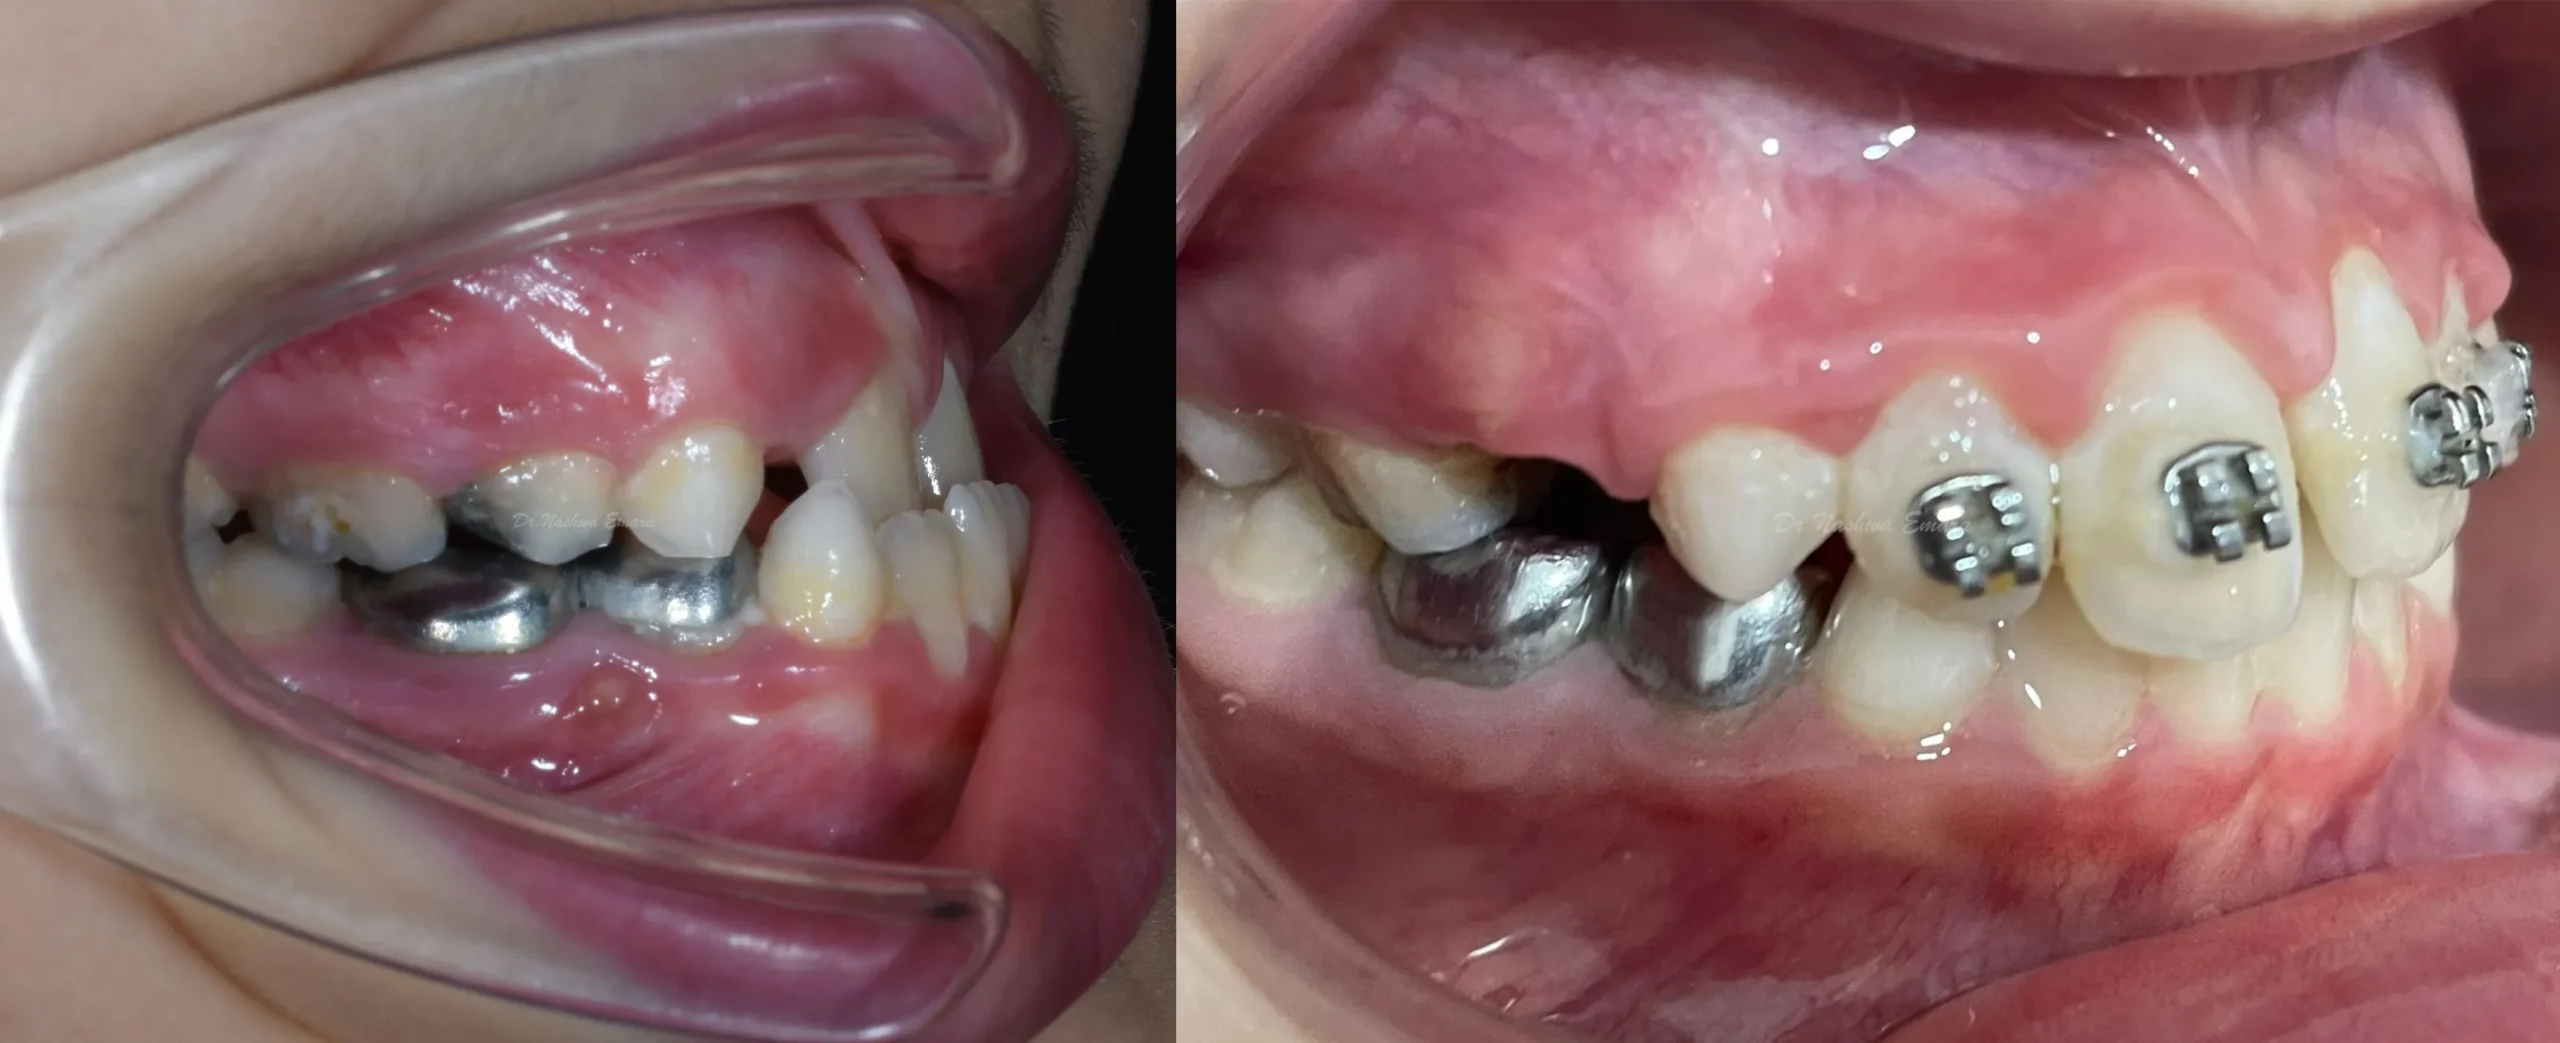

Children

Orthodontics